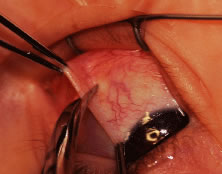

A Stevens' tenotomy hook is passed by the surgeon into the incision and is rotated so that it can be slid underneath the muscle insertion with the tip of the hook held tangential to the globe (Fig. 12). The hook should be passed 2 to 3 mm posterior to the expected location of the muscle insertion. Care is taken not to incorporate intramuscular septum or other adventitial tissue on the hook. When the lateral rectus muscle is secured with the Stevens' or Jameson muscle hook, care should be taken not to bring the inferior oblique muscle up to the insertion (Fig. 13). When the muscle is secured with the Stevens' hook, the hook and the inferior edge of the muscle insertion are elevated and a Jameson muscle hook is passed between the tented muscle tissue and the sclera to secure the muscle at its insertion (Fig. 14). Care is taken to include the entire insertion of the tendon on the hook. The tip of the Jameson hook is gently elevated by depressing the heel of the hook. This maneuver helps to ensure that the entire tendon of the muscle remains captured on the hook. A Stevens' tenotomy hook is placed in the incision, this time anterior to the insertion beneath the conjunctiva (Fig. 15). The Stevens' hook is passed posterior over the orbital surface of the muscle (Fig. 16). Gentle pressure on the Stevens' hook is directed posterior so that the check ligaments and Tenon's tissue that overlie the muscle belly are separated from the muscle capsule with blunt dissection. The hook usually is passed posterior for about 10 mm. When recessing a lateral rectus, attachments between the underside of the lateral rectus and inferior oblique are broken (Fig. 17). Two or three passes over the muscle are made, and, with simultaneous countertraction on the Stevens' hook and the Jameson hook, the conjunctiva is elevated and pulled over the tip of the Jameson hook (Fig. 18A and B).